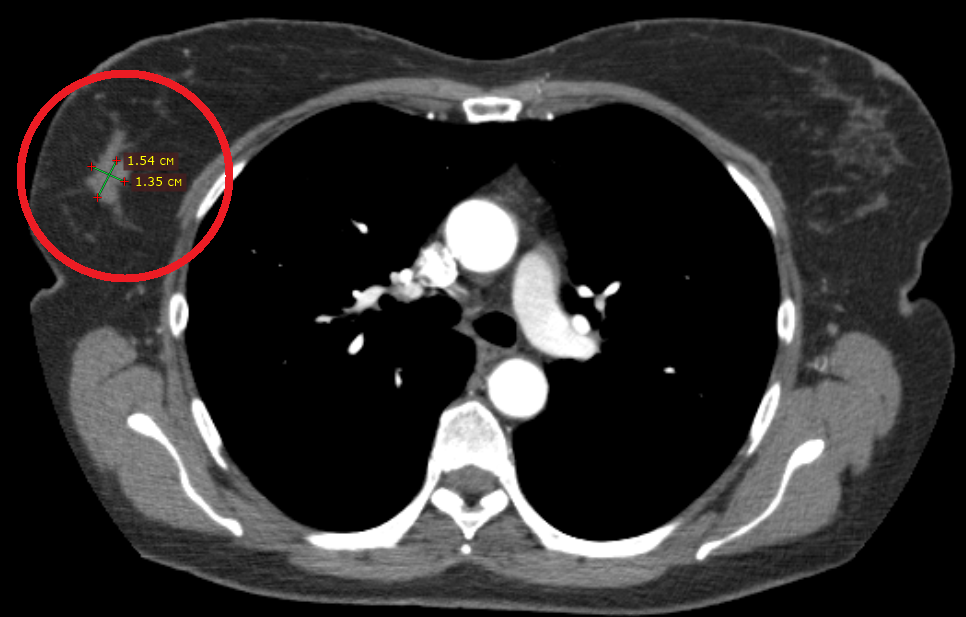

По данным компьютерной томографии всего тела с контрастированием признаки отдаленного метастазирования выявлены не были, но определился округлый подозрительный лимфоузел в правой подмышечной области. Размеры опухоли по КТ определились как 19х13.5х19 мм.

В центре красного круга определяется округлый подмышечный лимфоузел